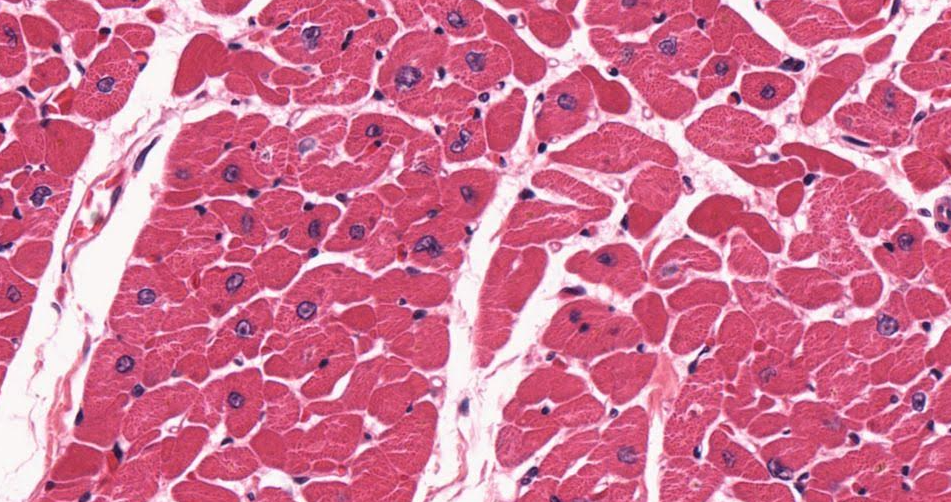

Tecido muscular (músculo cardíaco, em corte transversal).